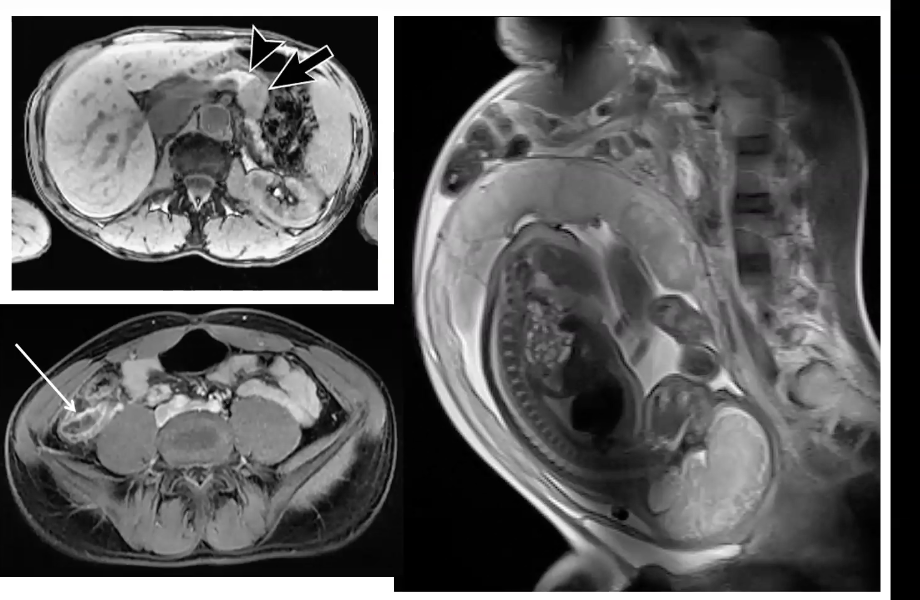

Different phase of contrast